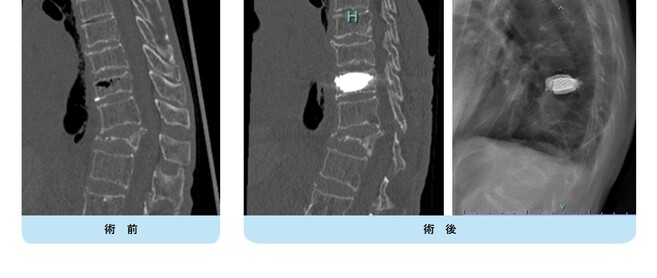

骨粗鬆症・脊椎椎体骨折

近年、高齢化社会に伴い骨粗鬆症を起因とする脊椎椎体骨折(いつの間にか骨折)が増加し、疼痛や寝たきりなどのADLの低下が問題となっています。多くの椎体骨折は局所後弯(曲がった背中)を生じることはあってもコルセットの装着などで通常そのまま骨癒合が得られ治ります。しかし、一部においては骨癒合が得られず偽関節となり強い痛みを生じたり、徐々に圧潰が進行し遅発性麻痺による歩行障害を生じたりすることがあります。これらに対する治療としては様々な方法がありますが、それぞれ一長一短があり、患者さんの全身状態、合併症、生活環境など考慮し治療方針を決定する必要があります。

骨粗鬆性椎体骨折の癒合遷延例や偽関節例で圧潰がひどくないタイプに対しては、低侵襲なセメント治療法であるBKP(BaloonKyphoplasty:バル-ン椎体形成術)という方法で治療することが可能です。BKP治療法の適応は、原発性骨粗鬆症による脊椎椎体骨折で十分な保存的加療によっても疼痛が改善されない患者さん、および多発性骨髄腫または転移性脊椎腫瘍による有痛性脊椎椎体骨折で、既存療法に奏功しない患者さんです。

BKP治療法は脊椎椎体骨折によりつぶれた背骨に、背中側から細い針を2か所(1cm程度)差込み、骨の中で風船を膨らませて、つぶれた骨の形を元に戻した後、空いた空間に骨セメントを詰め、脊椎椎体骨折の痛みをとるという治療法です。実際には手術治療を要する多くの骨粗鬆性椎体骨折は大なり小なりの後壁損傷を認め、その場合には罹患椎体にセメント充填を行いつつ上下の椎体にスクリューを挿入してロッドで架橋することにより補強・安定化を施しています。

不安定な椎体骨折に対してはBKPに後方固定を併用して再圧潰を防ぎます。

骨折部にセメントを注入し、金属を使用して補強しています。圧潰が高度で下肢が麻痺している場合には椎体置換術を行います。

近年は圧潰のやや進んだ骨粗鬆性椎体骨折に対して、骨折部にチタン製のステントを挿入してその中に骨セメントを充填するといった新しい手術方法で良好な治療成績が得られています。軽微な後壁損傷を伴った骨粗鬆性椎体骨折にも有用で、今後は治療成績が安定すればもっと適応範囲が広がることが予想されます。

第11胸椎椎体骨折を認めます。骨折部には黒いギャップが存在し、偽関節を呈しています。軽微な後壁損傷も認めます。第1腰椎は椎体骨折後の楔状化変形を認めますが、癒合しています。

骨折部にステントの殻を挿入し、ステント内に骨セメントを充填して治療しました。背中に5mm程度の切開を2か所おいて施します。ステントにより再圧潰が防がれ、また隣接椎体に対する負担も軽減されることが報告されています。